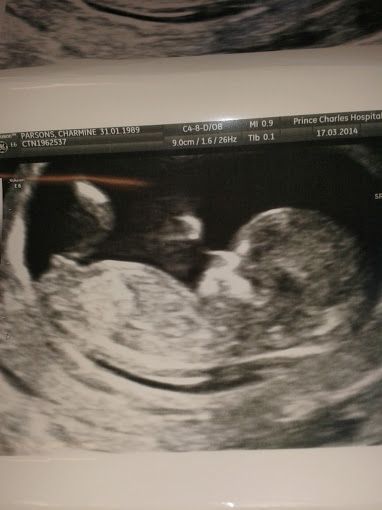

These are my 12wks 3 days scan pics from today, the sonagrapher had some really good pics on the screen but the angle of the baby's position is throwing me a bit on the pics she took & zoomed in, they were crystal clear to see first hand though xx Attachment 17670Attachment 17671Attachment 17672